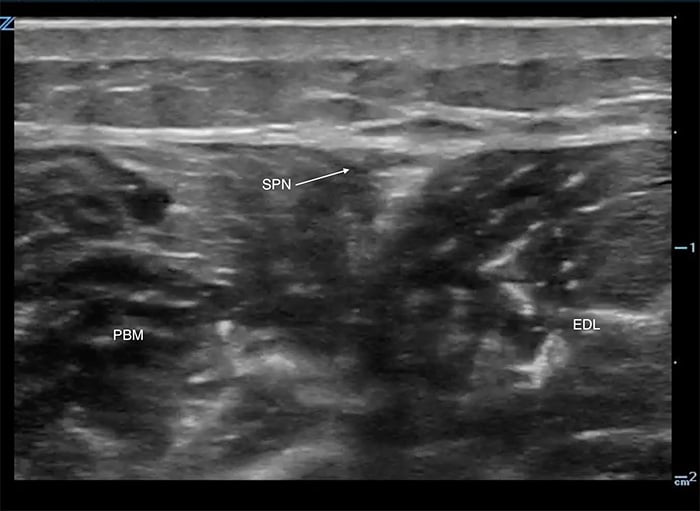

- Follow the fibula proximally to its midpoint where the peroneus brevis and extensor digitorum longus muscles are seen (Figure 1).

- These two muscles meet above the fibula.

- The superficial peroneal nerve travels in their superficial border and is seen as a hyperechoic oval or triangular shape.

Figure 1. Superficial peroneal nerve, proximal